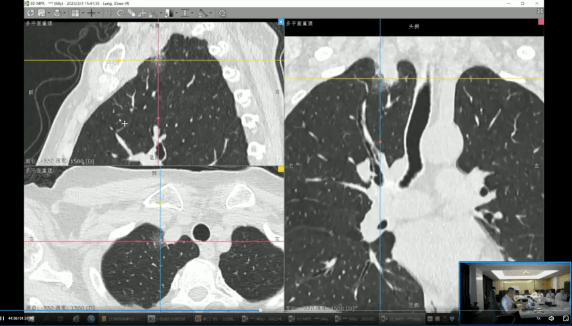

AI取影像手艺立异:集团积极结构人工智能取前沿影像手艺,健康集团昆明核心正式被云南省平易近营病院协会脑卒平分会授予“副从任委员单元”称号。“人工智能前沿手艺使用示范核心”等维度持续赋能沉点专科扶植及慢病办理办事系统,